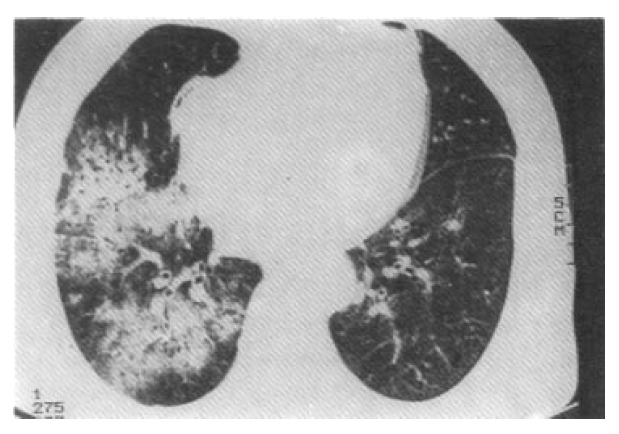

Therapy was initiated on January 22, with hemodialysis thrice weekly, and on January 25, with intravenous methylprednisolone 0.5g/day for 3 days, followed by prednisone 75mg/day(1mg/Kg) orally. Cyclophosphamide 150mg/day(2mg/Kg) was also given orally. She gradually improved but, on January 31, she complained of dyspnea. Chest X-ray showed homogeneous, ill-defined, patch consolidation on right lung field(Fig. 4). Hemoglobin was 5.0g/dL, platelet 157,000/mm3 and HRCT showed diffuse pulmonary hemorrhage(Fig. 5) and bronchoscopic examination showed fresh oozing blood from distal airway. Subsequently, diffuse pulmonary hemorrhage developed in left lung field. She was treated with transfusion to a hemoglobin of 10.8g/dL, ventilator care and second intravenous methlyprednisone 0.5g/day for 3 days. After that, prednisolone 75mg/day and cyclophosphamide 150mg/day were also given orally.

Fig. 5.

HRCT of the chest shows nonsegmental ground glass opacity with air-bronchogram in the right lung field.

Recently, for prompt diagnosis and institution of treatment, patients who have circulating ANCA vasculitis and upper and lower respiratory tract symptoms have been designated as Wegener’s syndrome, including classic WG and WG vasculitis5). The major sites of involvement are ear, nose, throat, lung and kidney6). Other major sites of involvement include the skin, with a variety of manifestations, including leukocytoclastic vasculitis and pyoderma gangrenosum; the nervous system, the chief sign being mononeuritis multiplex; the eye, displaying redness indicative of scleritis or episcleritis; the orbit, with pseudotumor causing proptosis; and the joints, manifesting a mono- or polyarticular migratory arthritis6). Diffuse alveolar hemorrhage was reported in 4 cases among 27 cases with ANCA associated vasculitis5) and 6 cases among 77 WG cases7). Diffuse alveolar hemorrhage is manifestated characteristically with hemoptysis, breathlessness, a diffuse alveolar filling pattern on chest roentgenogram and a profound anemia, and developed in fulminant WG6). In diffuse alveolar infiltrate on chest roentgenogram in WG, careful differential diagnosis between alveolar hemorrhage and infections is needed.

In our case, DPH was diagnosed by clinical and laboratory features, HRCT and bronchoscopic findings. Bronchoscopic findings in 51 WG patients showed hemorrhage without identifiable source in 2 cases, such as our case, probably due to hemorrhagic alveolar capillaritis8). By analysis of clinicopathologic characteristics and ANCA in 43 patients with DPH, underlying diseases were idiopathic pulmonary-renal syndrome(l6 cases), WG(10 cases), polyarteritis(11 cases), and isolated pulmonary hemorrhage(6 cases)9). No patients showed thrombotic microangiopathy simultaneously.